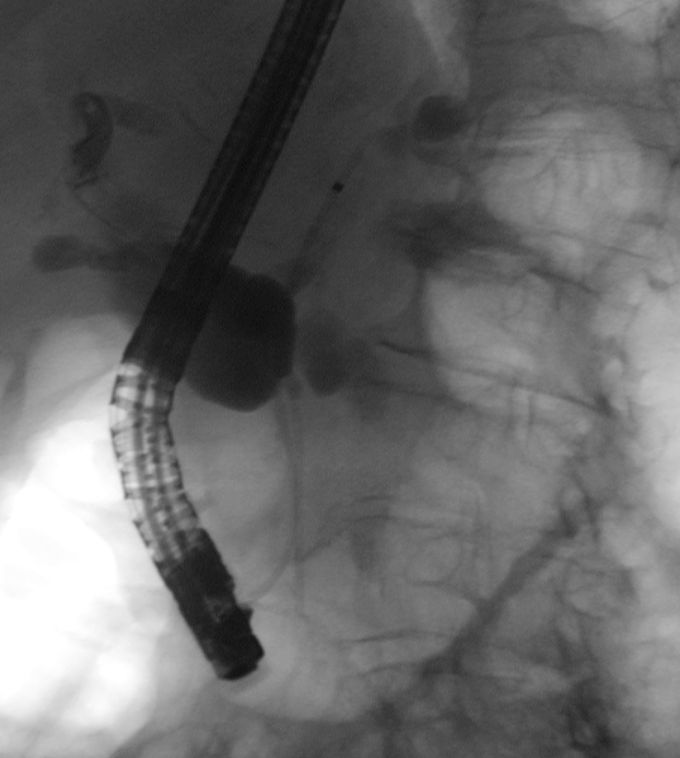

Die ERCP zeigt massiv erweiterte intra- und

extrahepatische Gallenwege. Ein Stent wird gesetzt.![]() |